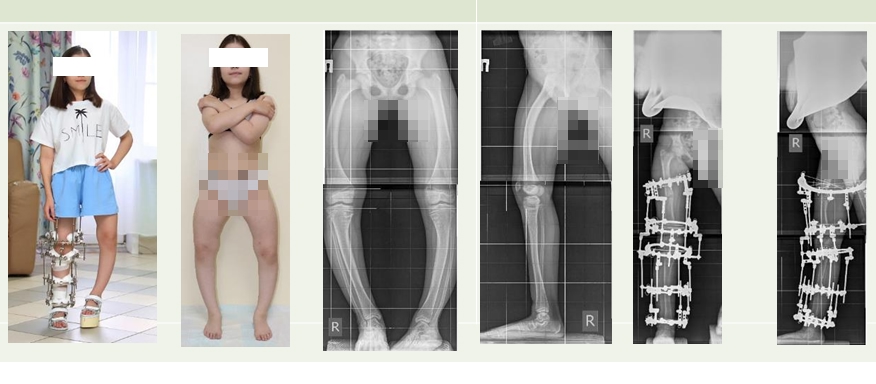

Многолетий опыт лечения пациентов с фосфат-диабетом имеется у отделения №17 Клиники нейроортопедии и системных заболеваний Центра Илизарова. Здесь успешно решают ортопедические проблемы, используя классику ортопедии и комбинацию методик, армируя кости данных пациентов интрамедуллярными спицами с биоактивным покрытием.

- При этом заболевании самые сложные деформации. Потому что они многоплоскостные, на всех сегментах. Кости становятся рыхлыми, вымывается фосфор, появляются множественные зоны переломов. Мы стараемся применять при лечении данных пациентов персонифицированный подход, используем самые эффективные методики, - рассказала Анна Аранович, профессор, д.м.н.